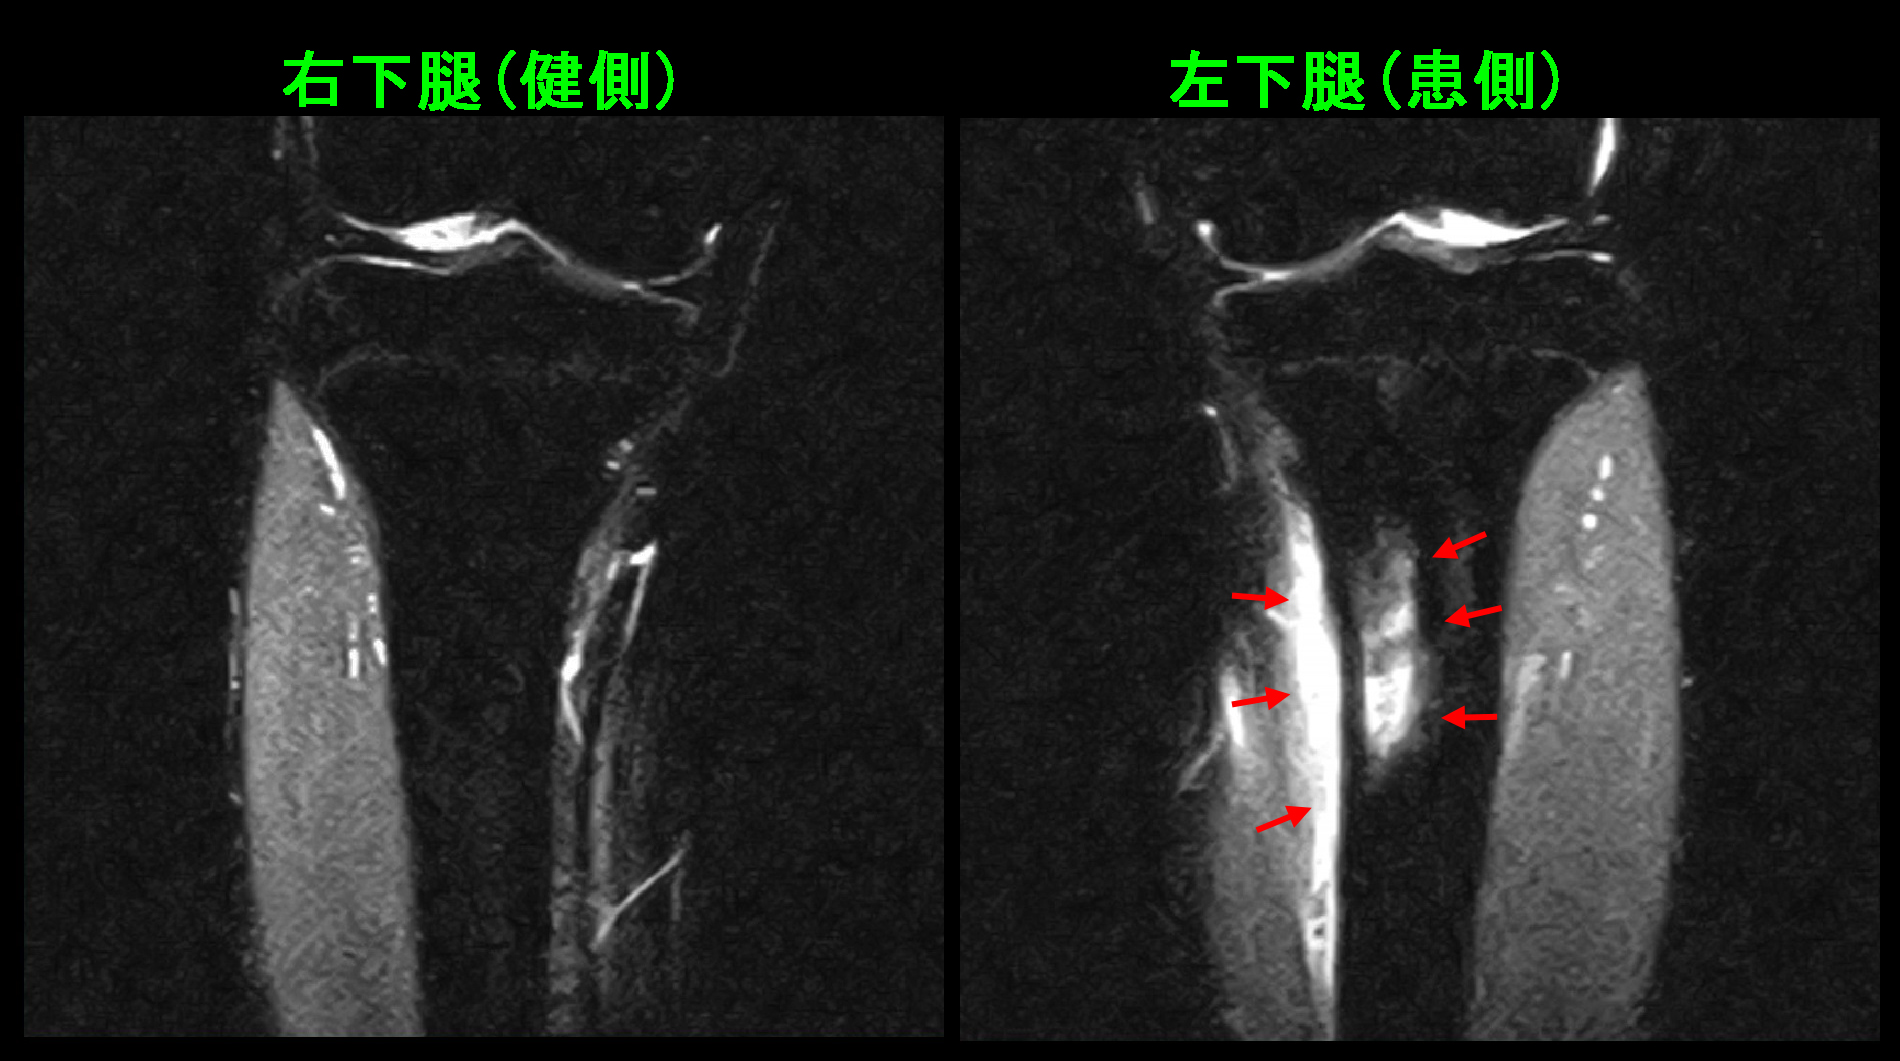

初診時Xp.jpg

レントゲン像の赤丸部分に痛みと圧痛(押して痛みがあるかどうか)を認めました。